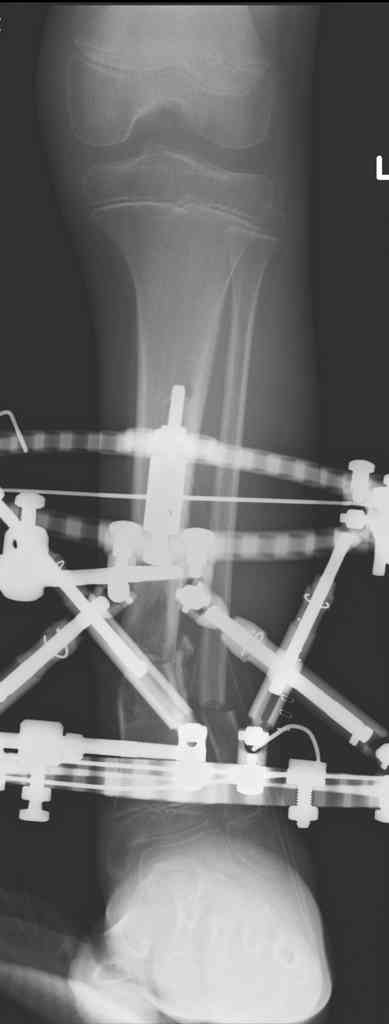

Re: case tibial defect

Another choice is simply perform shortening + posterior angulation with Ilizarov or TSF , than gradual correction of the angulation.After all apply third ring on the proximal tibia and start lengthening.

We had recently similar case in 14 years old boy with 45 mm bone defect after open tibial fracture.Boy doing excellent .This technique is not new, Sasha Lerner did it in Rambam , Rozbruch wrote also.

Another advantage of this techniqe is relaxation of soft tissue and possibility for closure even large defects of the skin.In your case I will apply ring on the foot and mid diaphysis of the tibia ,removal of the fibular plate,sindesmotic wire, and after correction of angulation on the proximal tibia.